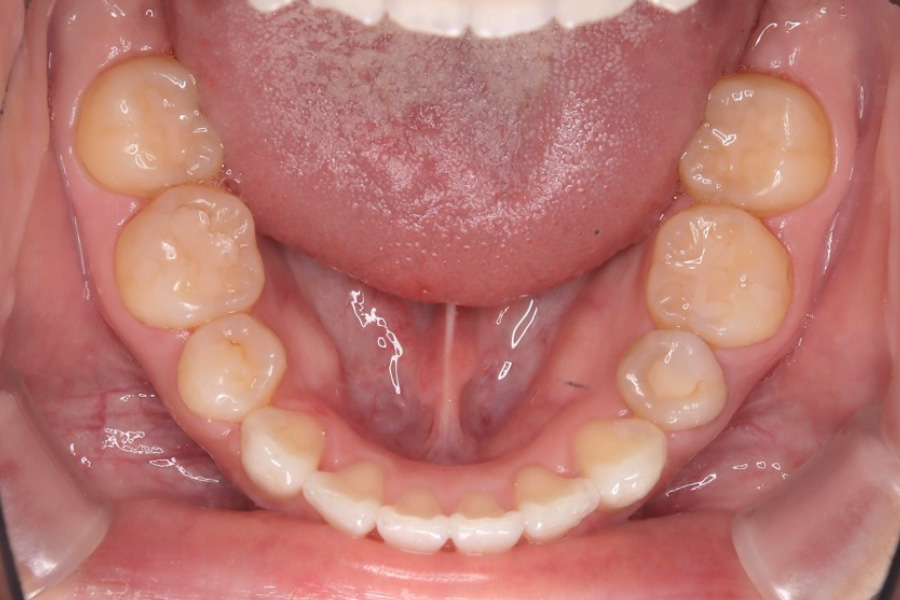

【20代女性】

歯のガタつき、突出感を

インビザライン矯正で治療したケース

治療後

主訴 歯のガタつき、突出感が気になる

治療内容 インビザライン矯正

小臼歯抜歯

治療に伴うリスク 矯正終了後は、リテーナーを指示通りに使用し、歯の後戻りを防ぐ必要があります。